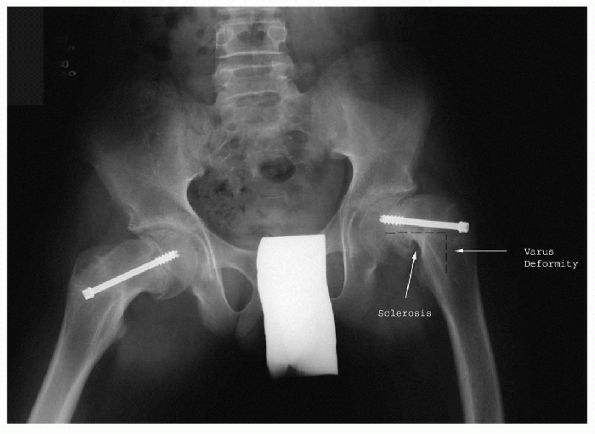

![]() |

Figure 11-4

Frog-leg radiograph of bilateral chronic slips, after pinning, demonstrating varus deformity and metaphyseal remodeling and sclerosis. |

Metaphyseal remodeling (Fig. 11-4)

Resorption of superior and anterior proximal metaphysis (see Fig. 11-4)

Sclerosis of posterior and inferior proximal metaphysis (see Fig. 11-4)

Varus deformity (see Fig. 11-4)